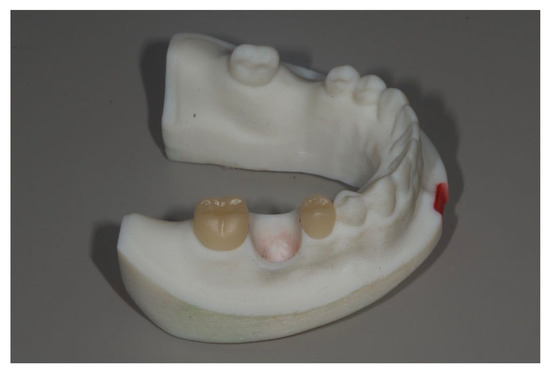

Figure 3.

Three kinds of removable dies with an implant and its corresponding CAD-CAM abutment were placed into the recipient sites. From left to right, Group Cent, Group L10, Group L15.